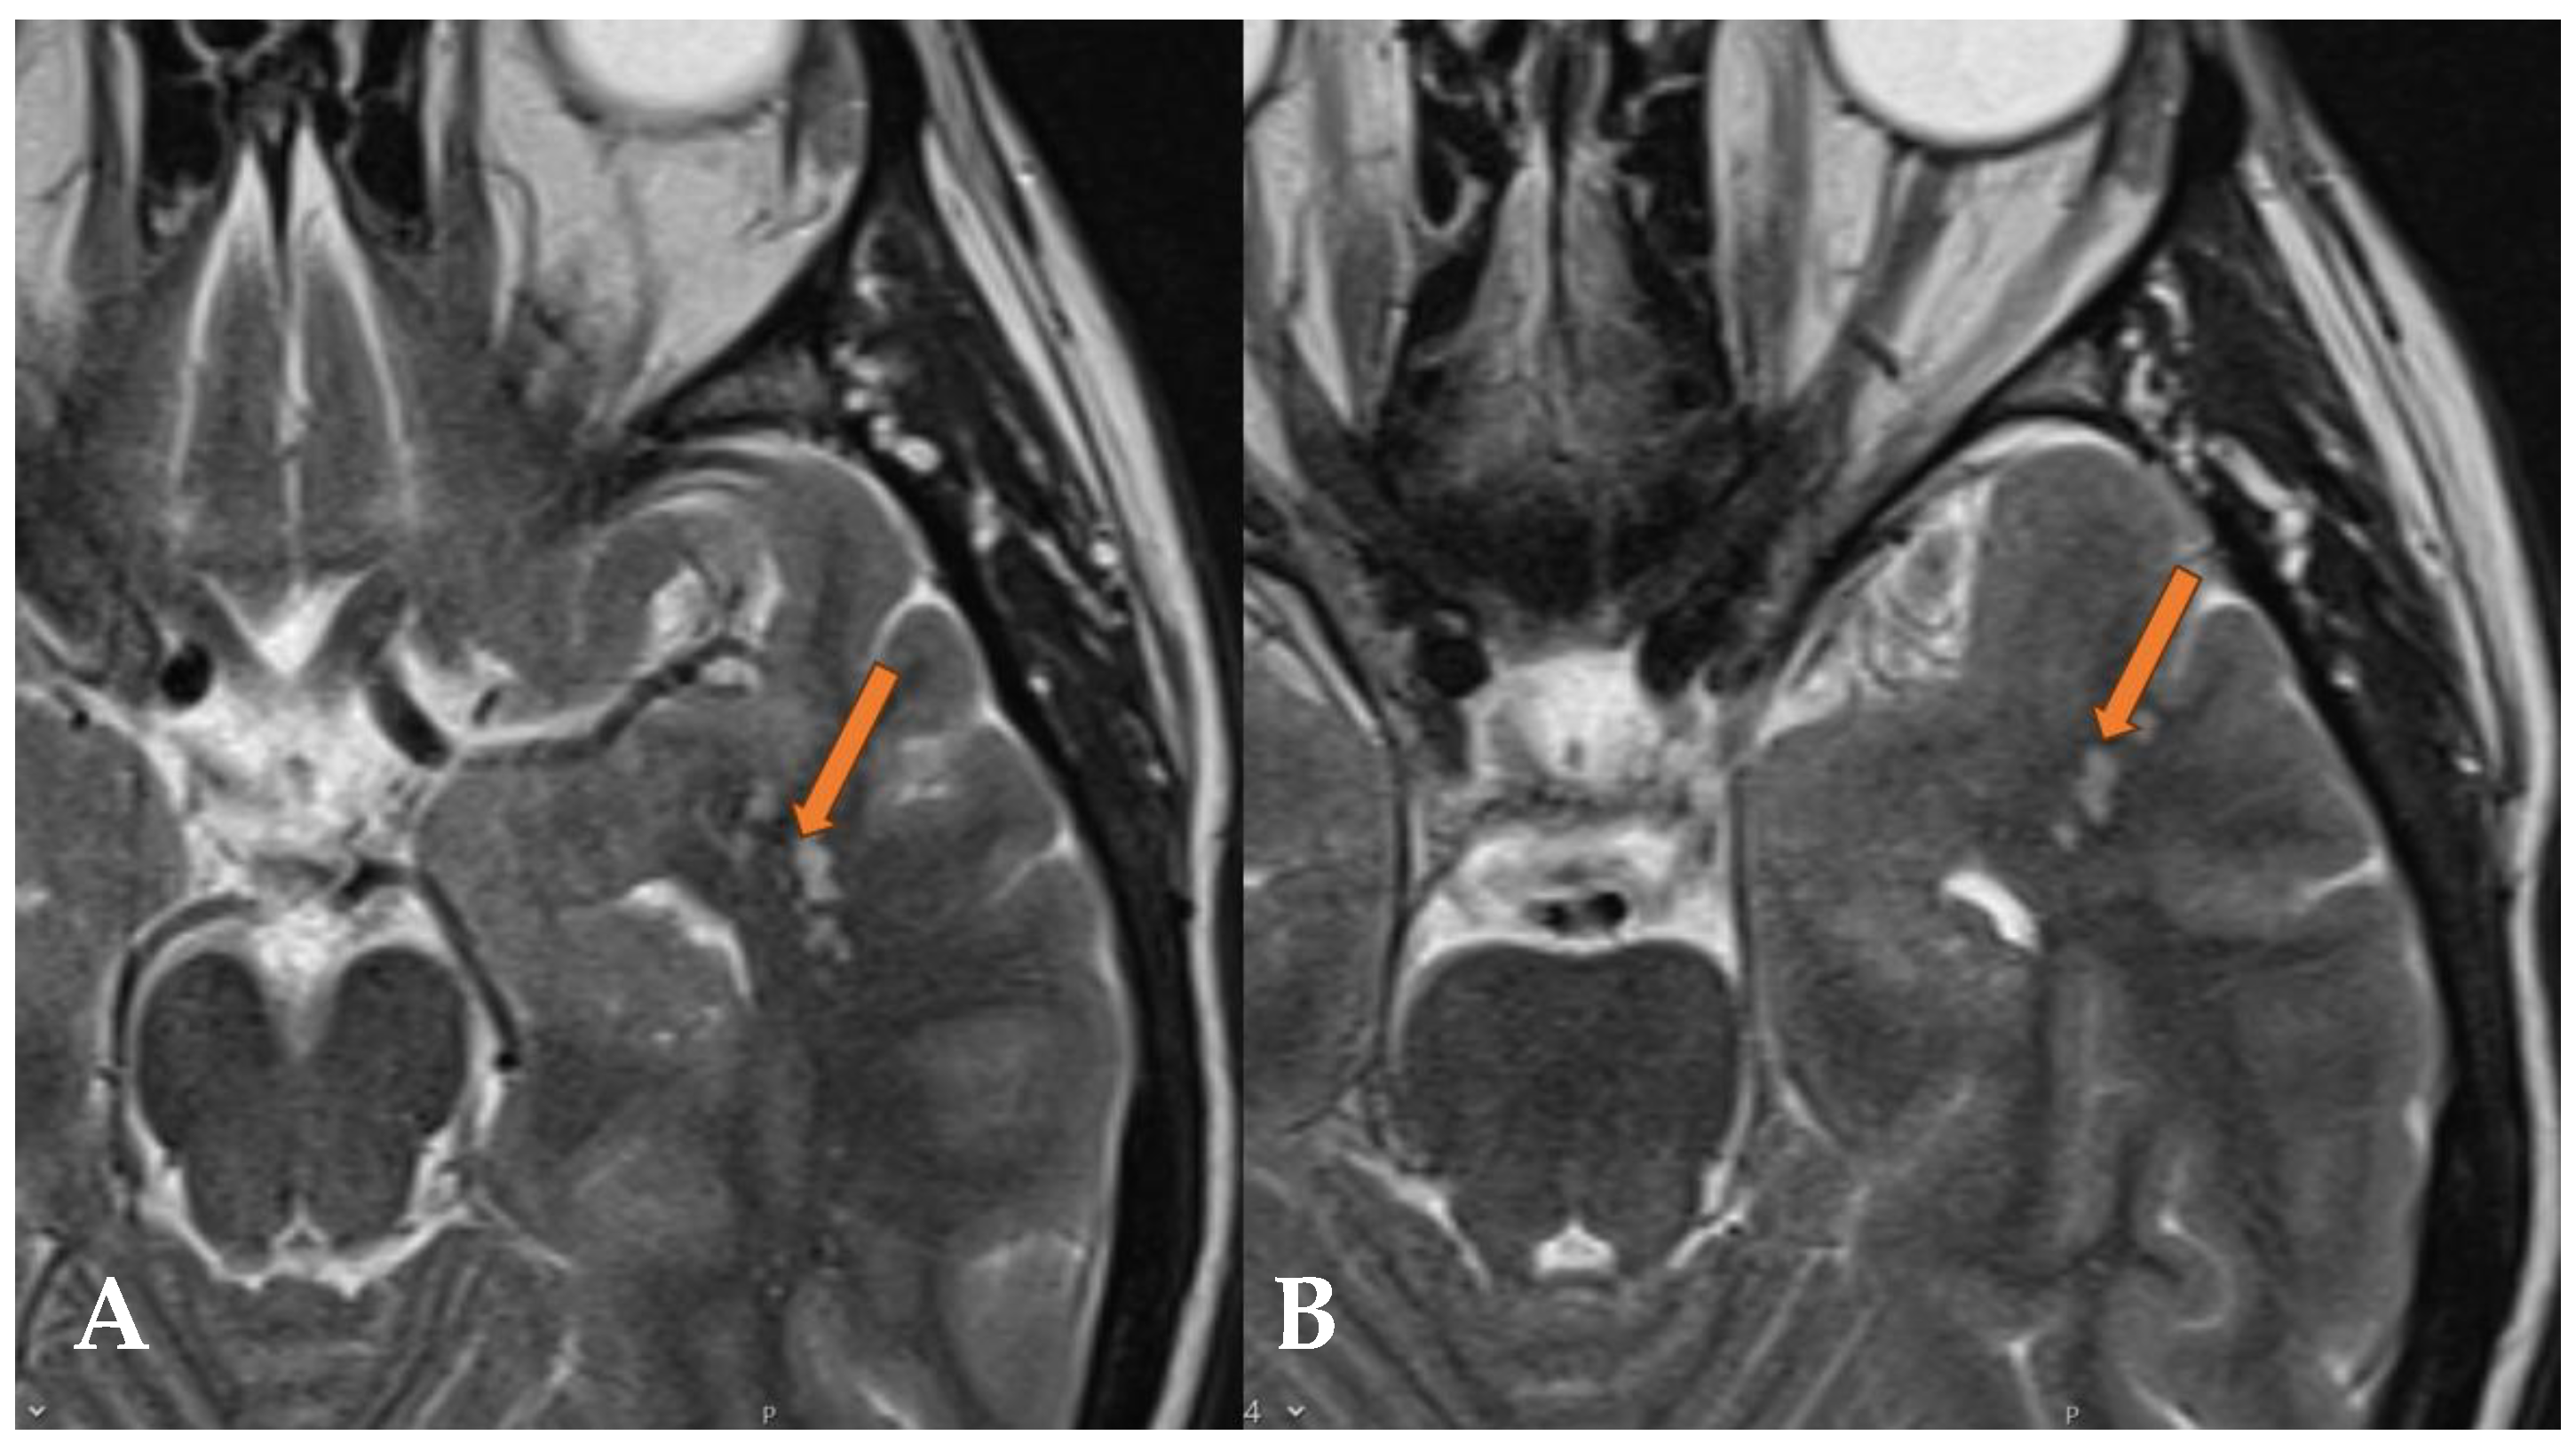

2.1. Case 1

2.2. Case 2

- Morassi, M.; Bagatto, D. Infratentorial Multinodular and Vacuolating Neuronal Tumor or Multinodular and Vacuolating Posterior Fossa Lesions of Unknown Significance? Clinico-Radiologic Findings from 2 Cases. World Neurosurg. 2020, 136, 58–61. [Google Scholar] [CrossRef]

- Lecler, A.; Bailleux, J.; Carsin, B.; Adle-Biassette, H.; Baloglu, S.; Bogey, C.; Bonneville, F.; Calvier, E.; Comby, P.-O.; Cottier, J.-P.; et al. Multinodular and Vacuolating Posterior Fossa Lesions of Unknown Significance. AJNR Am. J. Neuroradiol. 2019, 40, 1689–1694. [Google Scholar] [CrossRef]

- Abdelouahhab, H.; Guemmi, I.; Bouamama, T.; Kamaoui, I.; Nasri, S.; Aichouni, N.; Skiker, I. A rare cause of adult’s epileptic crisis: Infratentorial multinodular and vacuolating neuronal tumor. Radiol. Case Rep. 2022, 17, 4847–4849. [Google Scholar] [CrossRef] [PubMed]